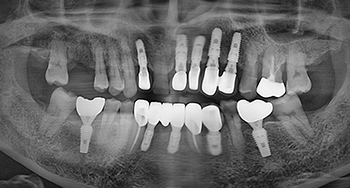

전체 임플란트

8개 이상의 임플란트를 수술하는 큰 수술이며, 환자의 구강구조를 정확히 파악해야 하기에 숙련도 높은 전문가의 식립이 필요합니다.

뼈이식 임플란트

식립 부위의 임플란트를 지지할 뼈가 부족한 경우 뼈이식재를 이용하여 뼈를 이식하는 난이도 높은 임플란트입니다.

임플란트 재식립

한 번 실패한 수술, 두 번은 더 어렵고 까다롭습니다. 임플란트 재식립이 필요한 경우 편한플란트치과에서 신중하게 재식립해드립니다.

만성질환 임플란트

환자 분의 건강 상태를 면밀히 파악하고 맞춤형 진료 프로토콜을 적용합니다. 당뇨 고혈압 등 만성질환이 있으셔도 안전한 진단이 가능합니다.